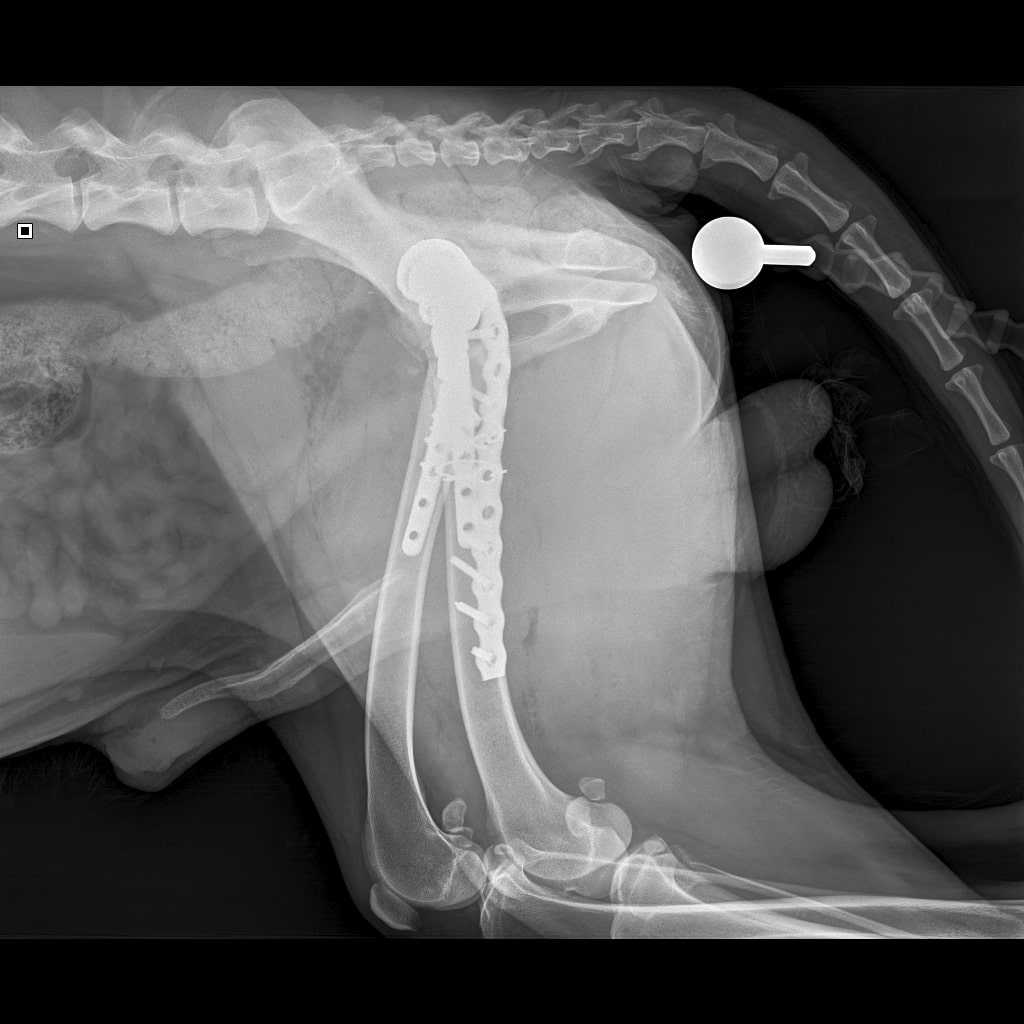

F37B4905-A77F-43B7-A3A7-4AAD9E739F82.jpeg

E6A744CC-768F-480D-8917-7FDAD53F05BD.jpeg

DA1A1524-BA63-434B-95BE-C121F7D5334F.jpeg

4D4A6426-4FE5-4417-ACCB-6DE53B57B90E.jpeg

За время противовоспалительной терапии снизилось воспаление и в левом тазобедренном суставе, но увы, форма головки бедренной кости и состояние шейки бедра , лучше не стали:(((

Операция однозначно нужна.

Снимки столь качественные, что их можно в учебник